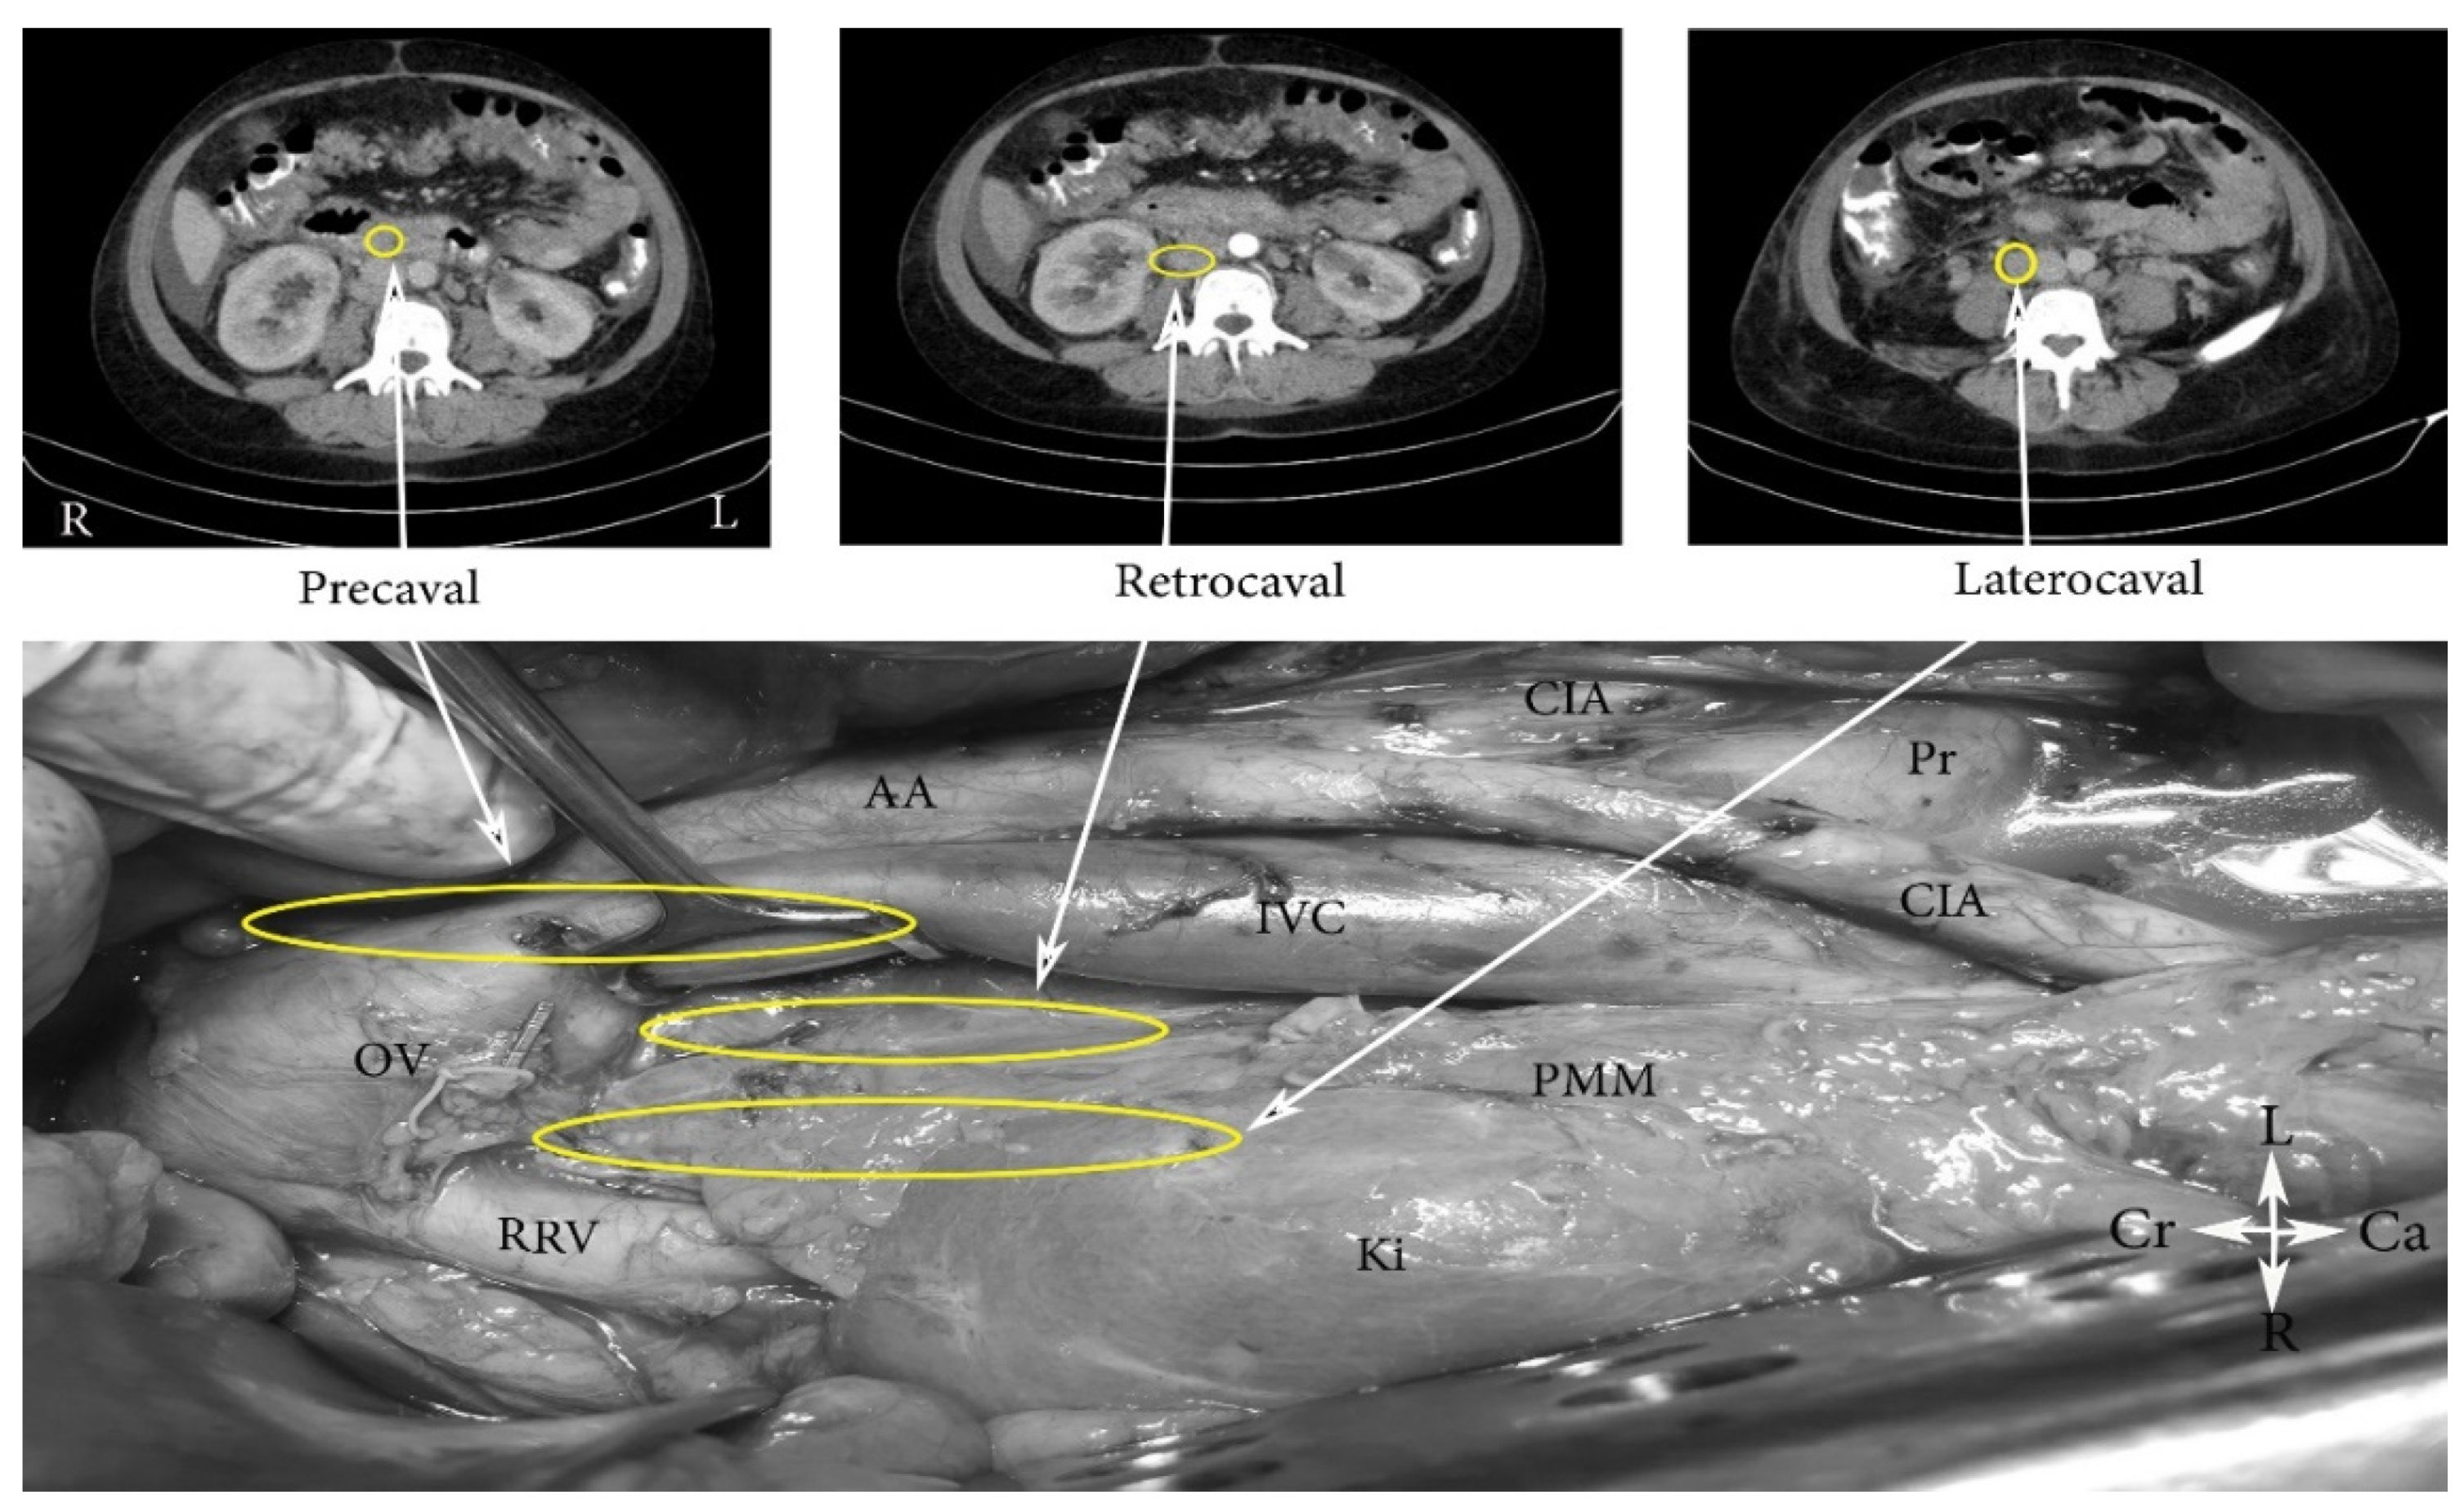

4. Regions and Their Boundaries during PALND

- (A)

- The high paraaortic (supramesenteric) region is limited: ventrally—LRV; medially—AA; laterally—ureter and Gerota fascia; dorsally—IMA; caudally—psoas major muscle.

- (B)

- The low paraaortic (inframesenteric) region is limited: ventrally by the IMA; medially—by the AA, dorsally—the left common iliac artery (CIA); laterally—the ureter and the Gerota fascia, caudally—the psoas major muscle.

- (C)

- The aortocaval or interaortocaval region (includes preaortic and precaval PALNs) is limited: ventrally—LRV, laterally—left—lateral aspect of the AA, right—lateral aspect of inferior vena cave, dorsally—AA bifurcation, caudally—prevertebral fascia, anterior longitudinal ligament and psoas major muscle.

- (D)

- The paracaval region (includes laterocaval and retrocaval PALNs) is limited: ventrally—right renal vein (RRV); dorsally—midpoint of the lateral aspect of right CIA, laterally—right ureter and right psoas major muscle, caudally—the psoas major muscle.